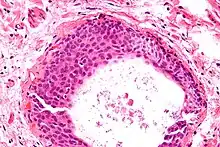

Micrograph of a cystic Walthard cell rest (lower right of image) within the connective tissue of a fallopian tube (tubal epithelium – upper left of image). H&E stain.

They appear as white/yellow cysts or nodules that can reach a size of 2 millimeters. They typically have elliptical nuclei with a long groove (along the major axis) – so-called "coffee bean" nuclei.